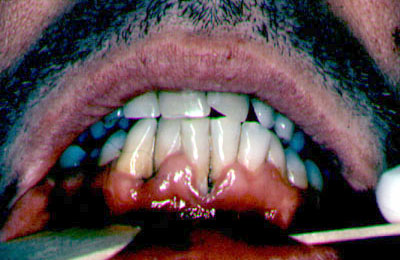

Las infecciones bacterianas involucran principalmente las estructuras  gingival y periodontal  y se reconocen 3 condiciones principales,  el eritema gingival lineal , la gingivitis ulceronetizante y la periodontitis ulceronecrotizante. En la actualidad estas lesiones son poco frecuentes debido a la eficacia de la terapia antiretroviral.

El eritema gingival  lineal aparece como una venda que rodea a las estructuras dentarias con un color rojo intenso y que suele involucrar la mucosa alveloar coronal, que puede sangrar espontaneamente.

La acumulación del placa es mínima; y no cede con las medidas profilácticas locales.